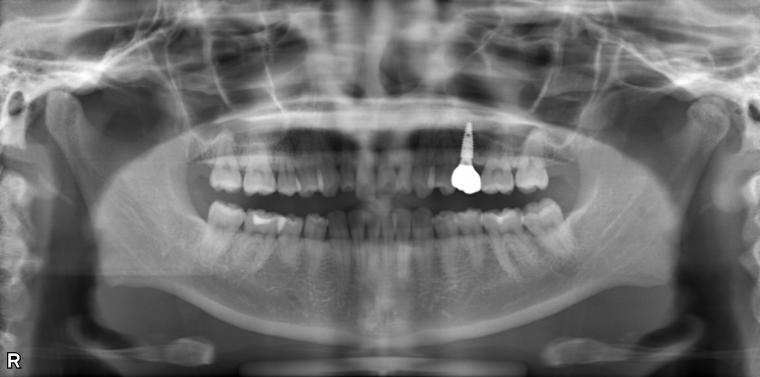

BEFORE

33歳女性/上顎1本欠損/インプラント埋込手術

左上第一小臼歯が先天性欠損のため無く、乳歯のままでしたが、乳歯も自然ダツリで抜けてしまったため、インプラントでの治療をご希望でご来院された患者さんです。

欠損部にインプラントが入り、現在は定期健診で拝見させていただいています。